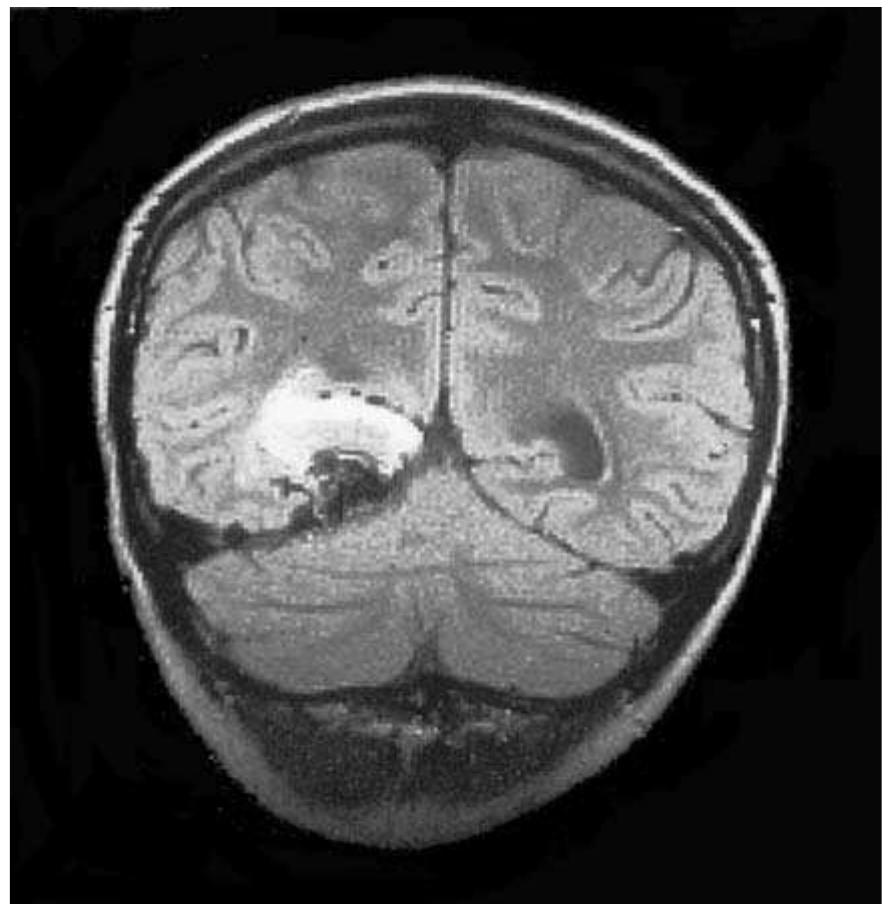

![Fig. 3.11 - Glioblastoma multiforme. The CT and MRI studies show a large, necrotic left hemispheric glioblastoma associated with extensive perilesional vasogenic oedema resulting mass effect and lateral subfalcian herniation. [a, b) unenhanced axial CT; ¢, d, b) PD-, FLAIR, T2-weighted MRI; f, g) T1-weighted axial and coronal MRI following IV Gd].](https://figures.academia-assets.com/35610716/figure_218.jpg)